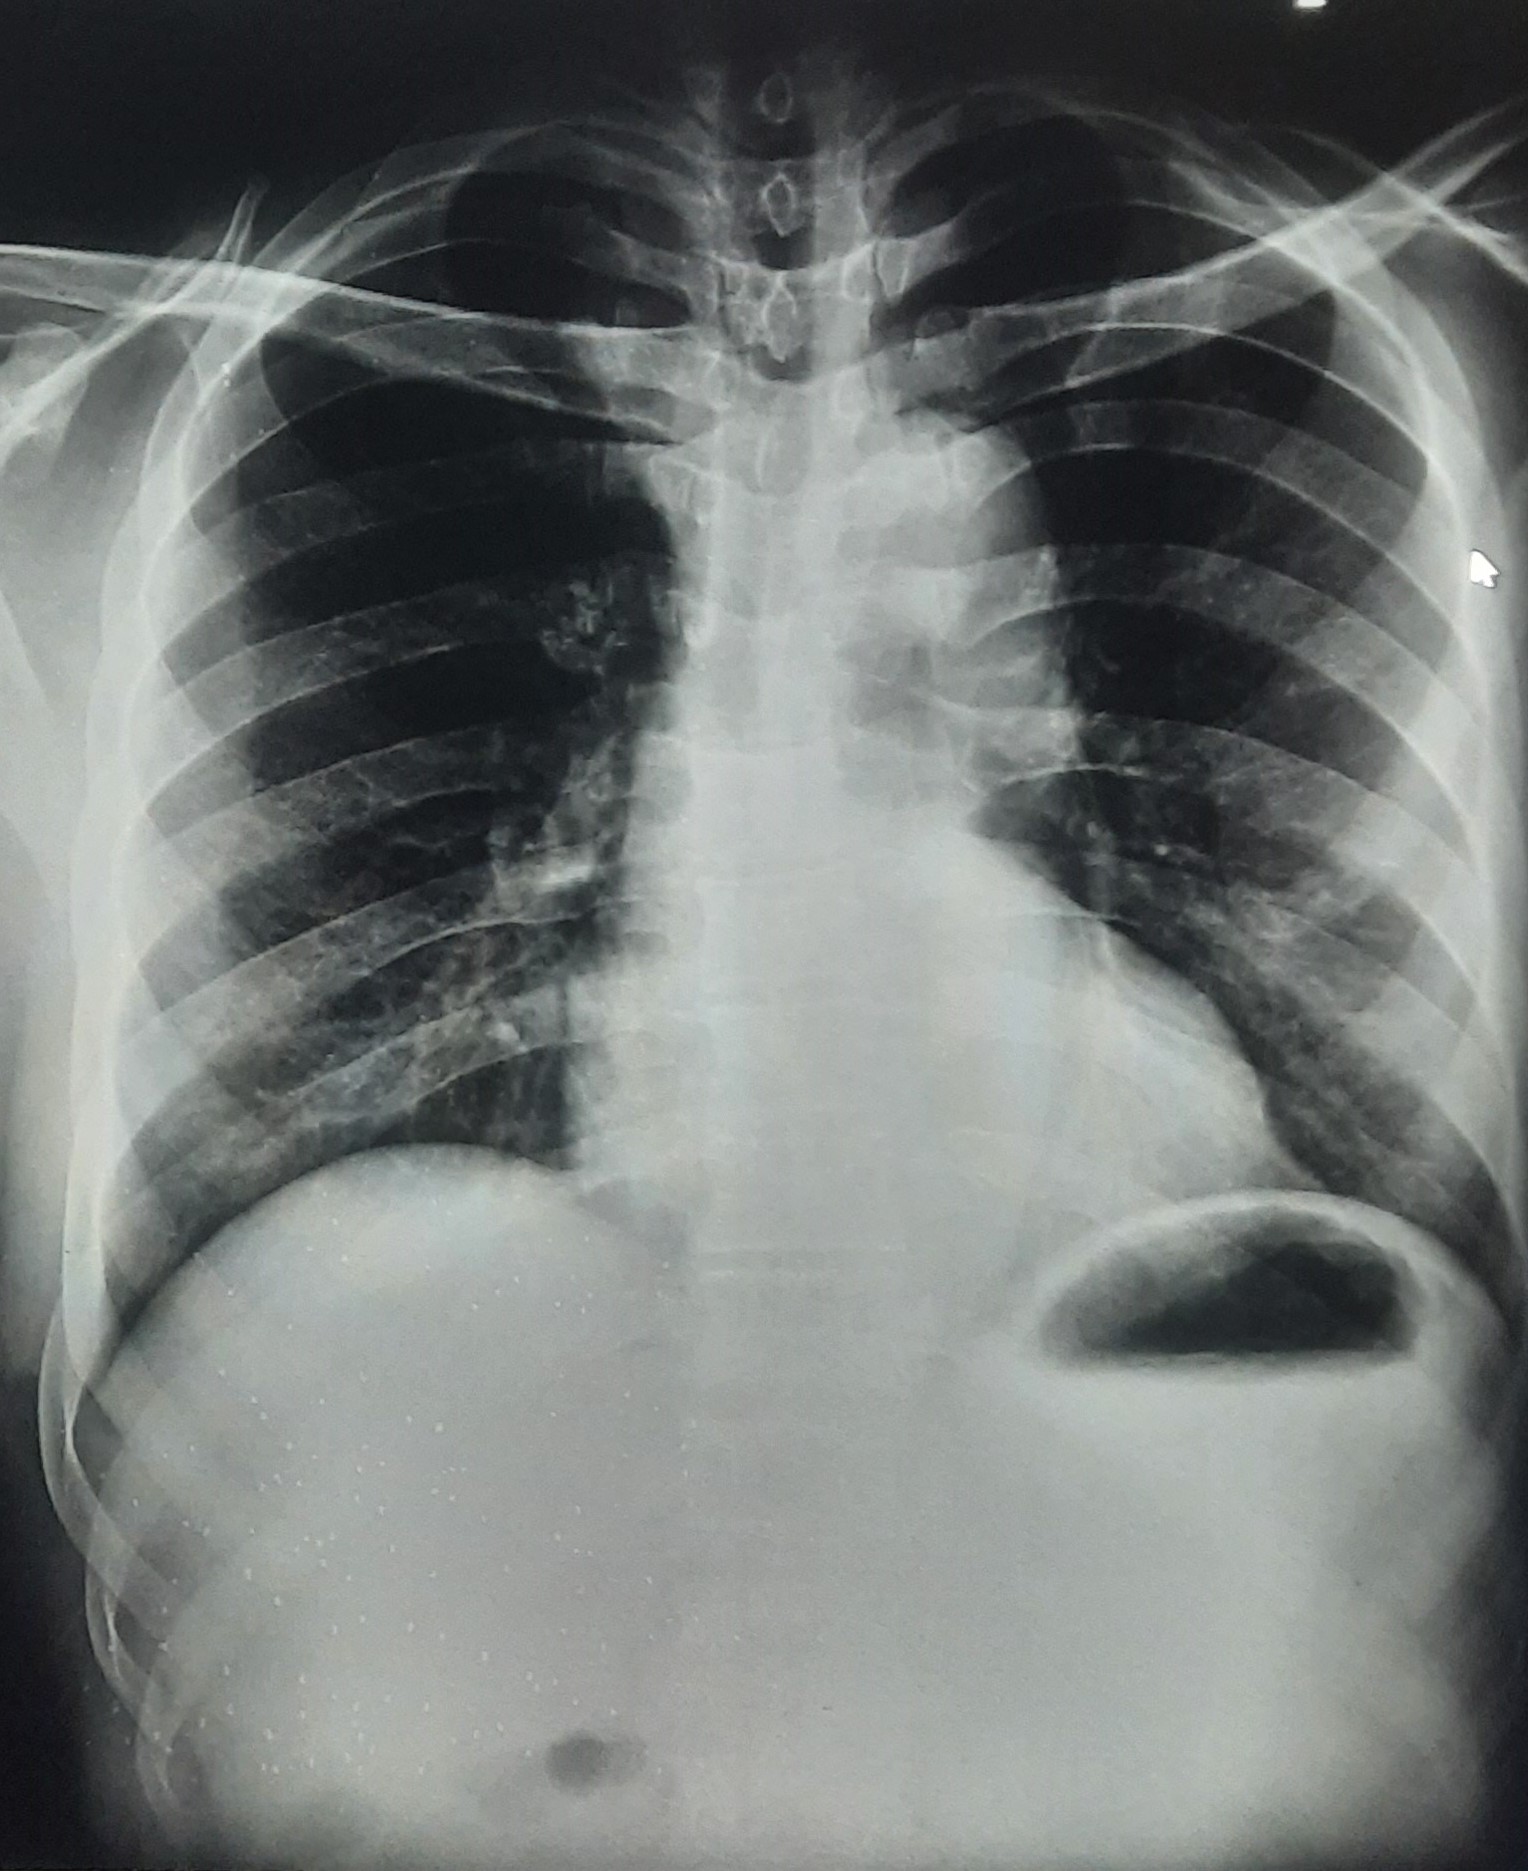

| 341 | IGGMC, Nagpur, Nagpur | P2 | 29-4131 | Tarzan Sahu | Consent taken on Paper | 34 Yrs. |

Provisional Diag : Bilateral Consolidations

Final Diag : Liver Disease |

Non-TB Case (Confirmed) | Faty Liver With Left Middle Zone, Lower Zone Consolidation With Symptomatic Effusion | Abnormality visible on x-ray |